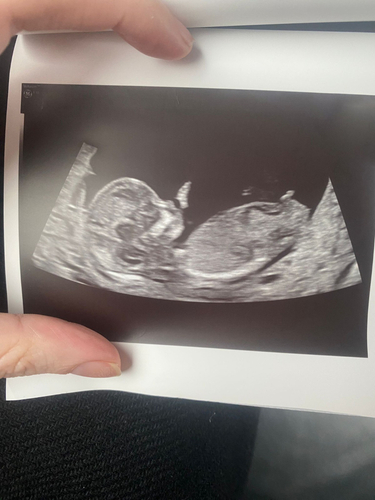

13 weken en 3 dagen

Helaas geen nub te zien